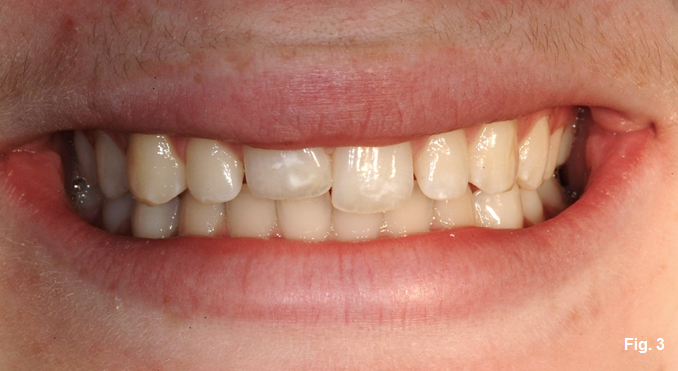

- Where is the smile line? The patient has a very low smile line and does not show the FGM (Fig. 3).